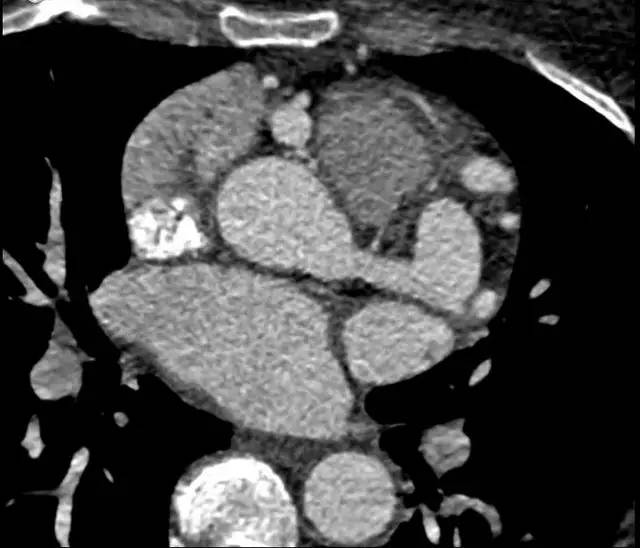

冠状动脉血管造影(CTA)回顾性心电门控扫描结果如下:

图 3

冠状动脉 CTA 是诊断该病理想的检查方法,轴位(图 1,2)及最大密度投影(图 3)CTA 显示右冠状动脉起源于主肺动脉。左冠状动脉主干显著代偿性扩张(图 4)。右冠状动脉未见狭窄及肌桥。左心室肥厚,左室射血分数为 55%。